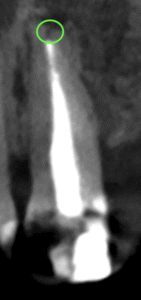

この部分を攻略できれば勝機がある可能性が90%あるだろう。

攻略できなければ60%だ。

どっちか?は治療しなければわからない。

それが根管治療の奥深い?ところなのかもしれない。

術後にPA,CBCTを撮影した。